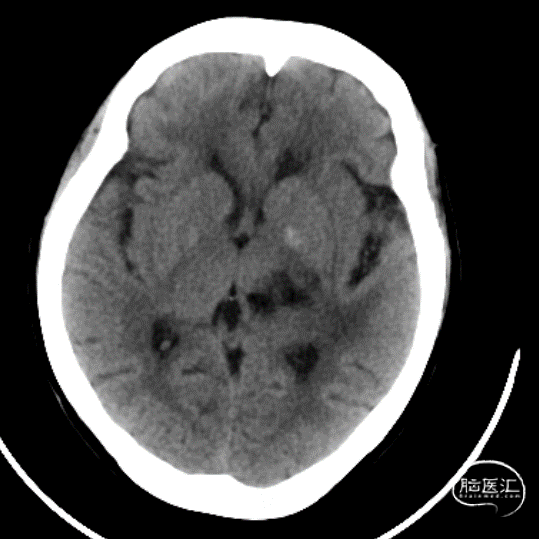

术后影像

Post-op-D1

Post-op-D2